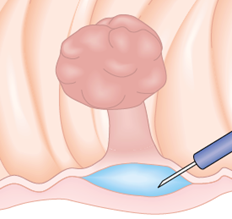

Mucosectomia é o procedimento realizado quando há necessidade de retirada de lesões maiores do trato gastrointestinal.

O exame de Mucosectomia é realizado através de injeção de liquido embaixo da lesão, através de uma agulha específica. Com isso a lesão se destaca das camadas mais profundas do intestino, diminuindo o risco de perfuração.

A retirada da lesão é feita com uma alça de polipectomia e o material é encaminhado para estudo anatomopatológico (no microscópio) da mesma forma que ocorre nas biópsias.

O que é a polipectomia?

A polipectomia é a remoção completa de um pólipo permitindo assim o diagnóstico exato e muitas vezes a cura do próprio problema. Existem várias técnicas para a realização do procedimento que dependem do tamanho e do tipo de pólipo a ser ressecado.

Alguns pólipos não possuem a base alongada (pedículo), estes são chamados de pólipos sésseis. A remoção destes pólipos possui risco maior de perfuração do órgão pois como são planos ficam muito próximos da parede externa do órgão.

Mucosectomia

Para diminuir este risco, injeta-se com um uma agulha uma solução abaixo do pólipo para que ele levante e fique mais longe da parede do órgão. Após isto passa-se a alça diatérmica e realiza-se o

procedimento de polipectomia.